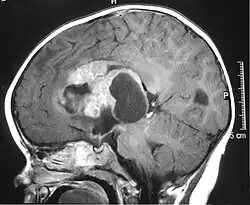

Atypowy nowotwór teratoidny (rabdoidny) (ang. Atypical Teratoid Rhabdoid Tumor, AT/RT) – rzadki guz mózgu wieku dziecięcego, o wysokim (IV° według WHO) stopniu złośliwości i często śmiertelny.

AT/RT jest rzadkim nowotworem. W USA zapadalność na ten typ guza wynosi 3:1 000 000, co daje 30 przypadków AT/RT diagnozowanych co roku. Corocznie przybywa 2500-3000 nowych pacjentów pediatrycznych z guzami ośrodkowego układu nerwowego, i około 3% z nich to AT/RT, chociaż odsetek ten może wzrosnąć wraz z lepszym różnicowaniem AT/RT i guzów typu PNET/medulloblastoma.

Przeżywalność pacjentów z guzem AT/RT wynosi około 11% u pacjentów poniżej 3. roku życia i ponad 70% u pacjentów starszych niż 3 lata[3].